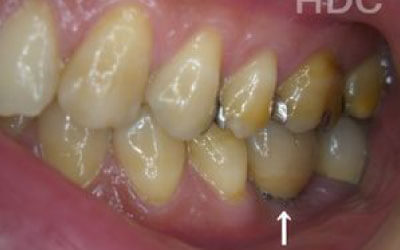

ブリッジ治療では、欠損部分の両側にある歯を大きく削らなければならず、場合によっては虫歯がなくても歯の神経を抜くことがあります。神経を抜いた歯に被せ物をすると、その歯は急速に弱くなり、寿命が短くなるリスクが高まります。

一方でインプラント治療なら、周囲の歯を削ったり神経を抜いたりする必要がないため、健康な歯を守りながら歯の寿命を延ばすことができます。